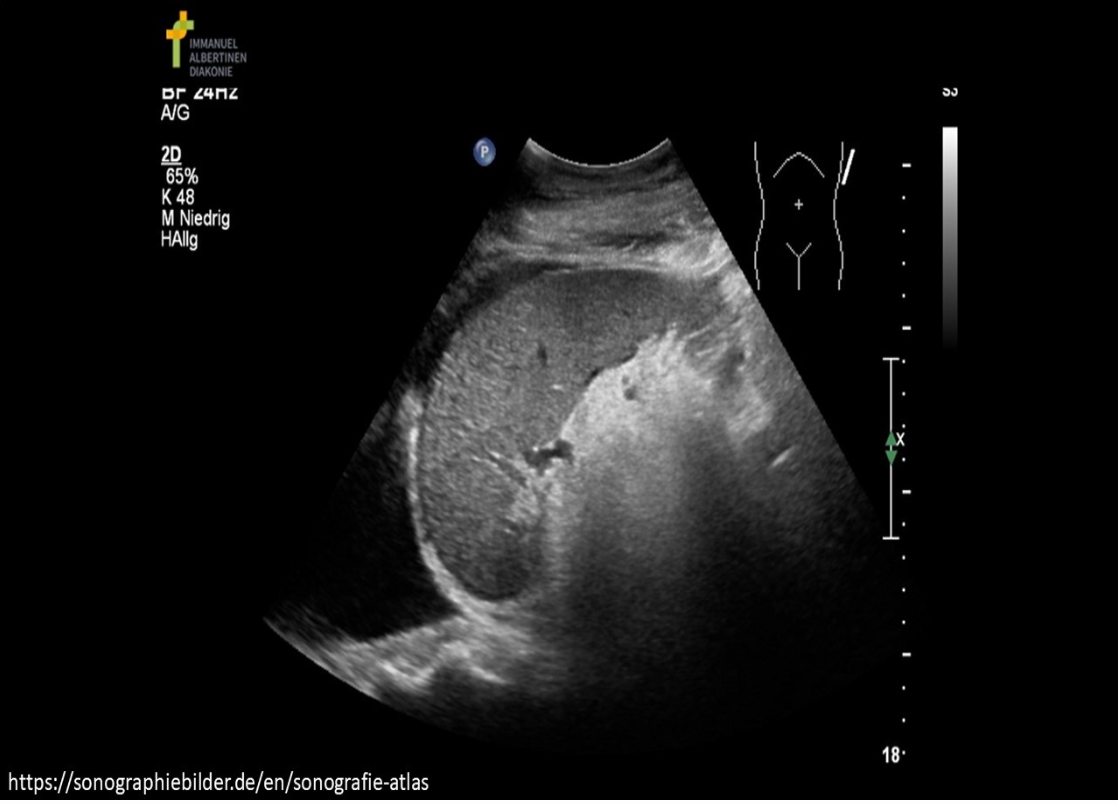

The image demonstrates a coronal view of the left upper quadrant. Where is free fluid documented on the image?

B. subphrenic space and pleural space

The image demonstrates a fluid above and below the diaphragm in the LUQ. There is moderate pleural effusion and mild ascites in the subphrenic space.